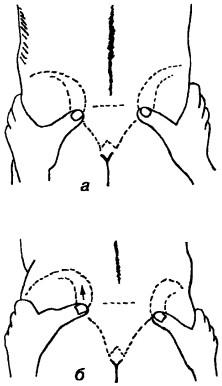

Ábra. 140. A képződésének mechanizmusát a sodrott kismedencei

csavart medence mechanizmus Cramer aszimmetrikus nutáció és forgása a keresztcsont tekintetében mind a kismedencei csontok (ábra. 140). Azon az oldalon, elmozdulás keresztcsont ponyvák előre és lefelé (ventrokaudalno), és másrészt a rendre tolódott felfelé és hátra (dorsokranialno). Azon az oldalon, a dőlés a keresztcsont olyan irányban ventrokaudalnom medence forog kifelé hosszanti tengelye körül a szemközti oldalon ez körül forgatjuk az elülső tengely áthalad a csípőizületi vápa. Ugyanakkor a medence, mintha rastopyrivat, symphysis történik relatív hígítása a szeméremcsont, hogy az aszimmetria a helyüket. Általában úgy tűnik, hogy egy csípő forgatva egymáshoz képest körül az első oldalsó gerinc. Külső forgása a medence az alsó fekvő felső hátsó csípő a legtöbb esetben okoz megfelelő elfordulását a külső lábak. Klinikai tünetek csavart kismedence következő: posterior csípőnyerget és egy hátsó éle a csípő gerincén alatt található az egyik oldalon, és az elülső AWN - az alábbiakban a szemközti oldalon. És csípőtaréj oldalon lehet ugyanazon a szinten. Lehet változatok, ahol akár elöl vagy hátul a gerinc marad szimmetrikus. Ezért a legfontosabb dolog - a hely meg nem felelés az első és hátsó tüskék és a csípőlapátból. Amikor egy csavart medence nem a blokkoló és visszaélés az ő helyzetét.

Az a jelenség, előre kórjelzô kimutatására elmozdulását sacroiliacális közös. Az orvos, míg a hátsó, a beteg figyeli a helyzet a hátsó csípő tüskék előtt és után hajlítás. Abban az esetben, csavart a medence vagy a gerinc-zheraspolozhennaya vissza során hajlítása eltolódott a koponya, mert ezen az oldalon a keresztcsont ponyvák előre és lefelé, ami feszültséget szalagok Mekheda keresztcsont és csípő, vetjük alá nagyobb tapadást. Különösen fontos az a jelenség, amikor a kezdeti helyzetben a szimmetrikus és aszimmetrikus hátsó - első tüskék (ábra 141.).